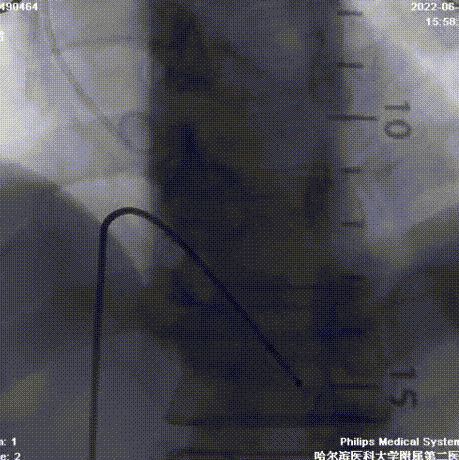

术中操作

造影检查入路

根部造影

球囊预扩

首次释放

二次释放

瓣膜释放完成

术中回收释放两次,释放过程中预估瓣叶增厚挤压瓣架的偏移下滑程度,适当调整瓣架初始植入深度,结合经颈动脉入路而对输送系统产生的血流冲击力适时调整输送系统和导丝张力,保证最大的同轴性,从而保证人工瓣膜充足且温和的锚定和脱钩时的最小形变。